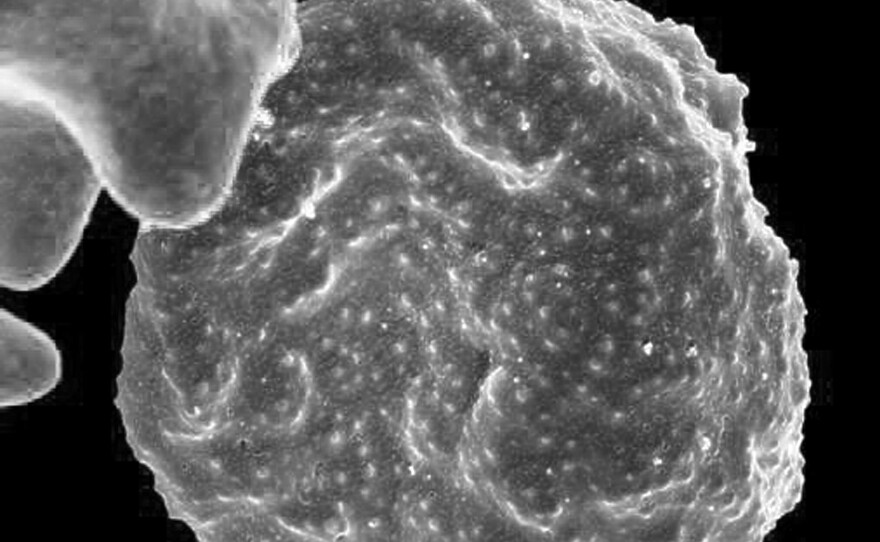

An electron microscope image of an infected red blood cell. The malaria parasite causes protrusions called "knobs" to form on the surface of the cell